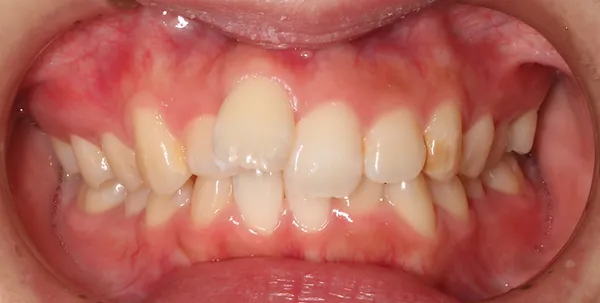

1矯正・マウスピース【治療例2】

治療前

治療後